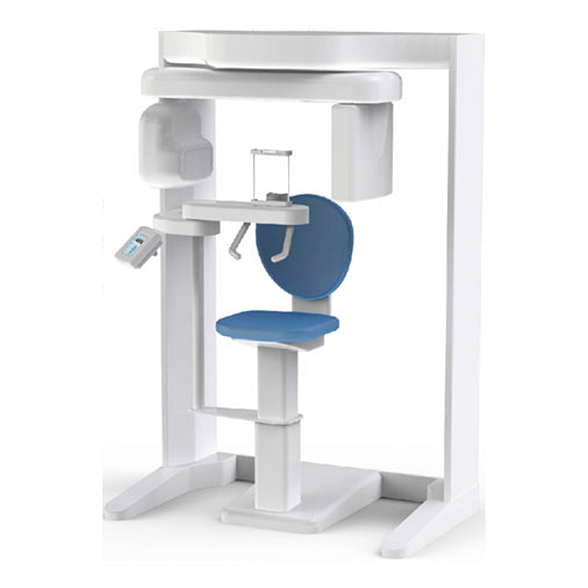

Gendex Pan eXam Plus 2D - дентальный цифровой томограф

Gendex Pan eXam Plus 2D: Цифровой панорамный томограф для точной диагностики

Цифровой панорамный томограф Gendex Pan eXam Plus 2D — это современное и надежное решение для оснащения стоматологической клиники или кабинета. Аппарат предназначен для получения высококачественных двухмерных панорамных снимков зубных рядов, что является основой для планирования лечения, имплантации, ортодонтической коррекции и оценки общего состояния зубочелюстной системы.

Gendex Pan eXam Plus 2D сочетает в себе проверенное качество бренда, интуитивно понятное управление и высокую детализацию снимков, что позволяет врачу ставить точный диагноз и повышает доверие пациентов к клинике.

- Эргономичный дизайн: Компактные размеры и открытая конструкция томографа минимизируют чувство дискомфорта и клаустрофобии у пациентов, включая детей и пожилых людей.

Технические характеристики Gendex Pan eXam Plus 2D

| Габариты (Ш x Г x В) | Примерно 1500 x 1800 x 2200 мм (зависит от конкретной комплектации) |

| Вес | Около 350 кг |